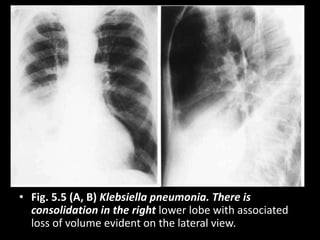

• Fig. 5.5 (A, B) Klebsiella pneumonia. There is

consolidation in the right lower lobe with associated

loss of volume evident on the lateral view.

• Fig. 5.5(A, B) Klebsiella pneumonia. There is consolidation in the right lower lobe with associated loss of volume evident on the lateral view.